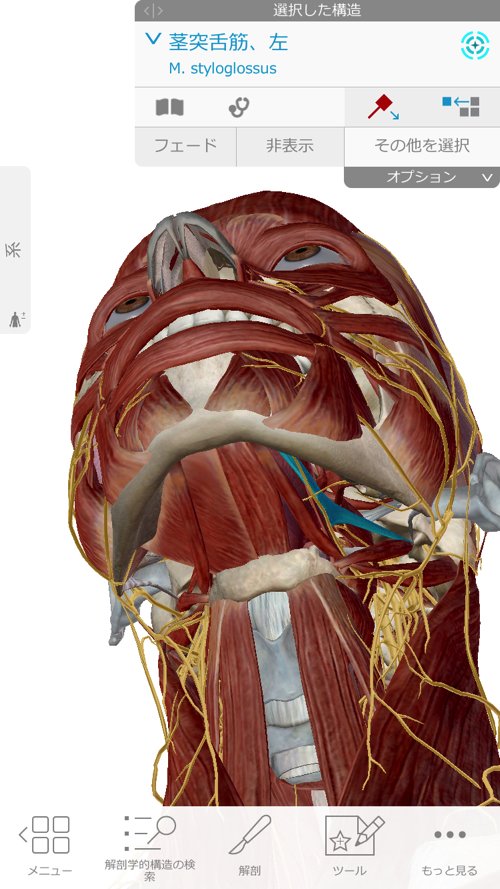

顎下から鎖骨、そして肘に向かうラインに硬直やヨジレが集中しています。

次に顎周りを緩めて首周りの硬直とズレをなくします。